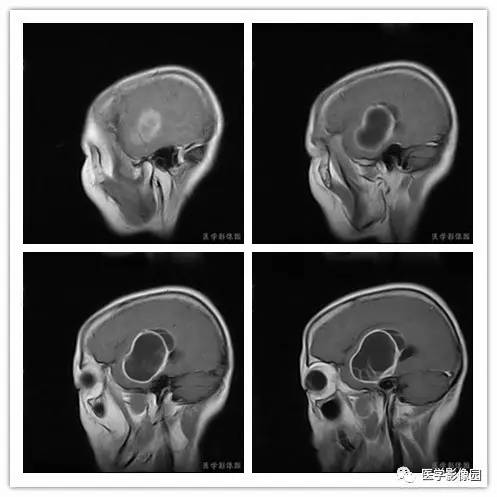

影像学表现:右侧颞叶深部区见一长T1、长T2囊样信号,成明显环形强化、未见明确结节影,没有FLAIR和DWI图,内见分隔,边界较清,周围水肿不明显,右侧脑室明显受压、颞角扩大,右侧脑沟明显变浅,脑中线结果向左偏移。

血管外皮细胞瘤好发于颅底、矢状窦或大脑镰旁、小脑幕等硬脑膜或静脉窦附近。肿瘤多呈分叶形或不规则形,少数可呈椭圆形或扁圆形。多数具有脑外肿瘤特点,与脑膜或大脑镰和小脑幕有广基底连接,少数与脑膜以窄基底连接,后都可能是由于肿瘤生长时间短而又生长体积较大。

1.肿瘤主要表现为等长T1 、等长T2 混杂信号影,偶可见短T1 或短T2 信号影,注药后,肿瘤增强明显但不均匀;

2.外形呈不规则分叶状;

3.半数以上的肿瘤与硬膜窄基底相连;